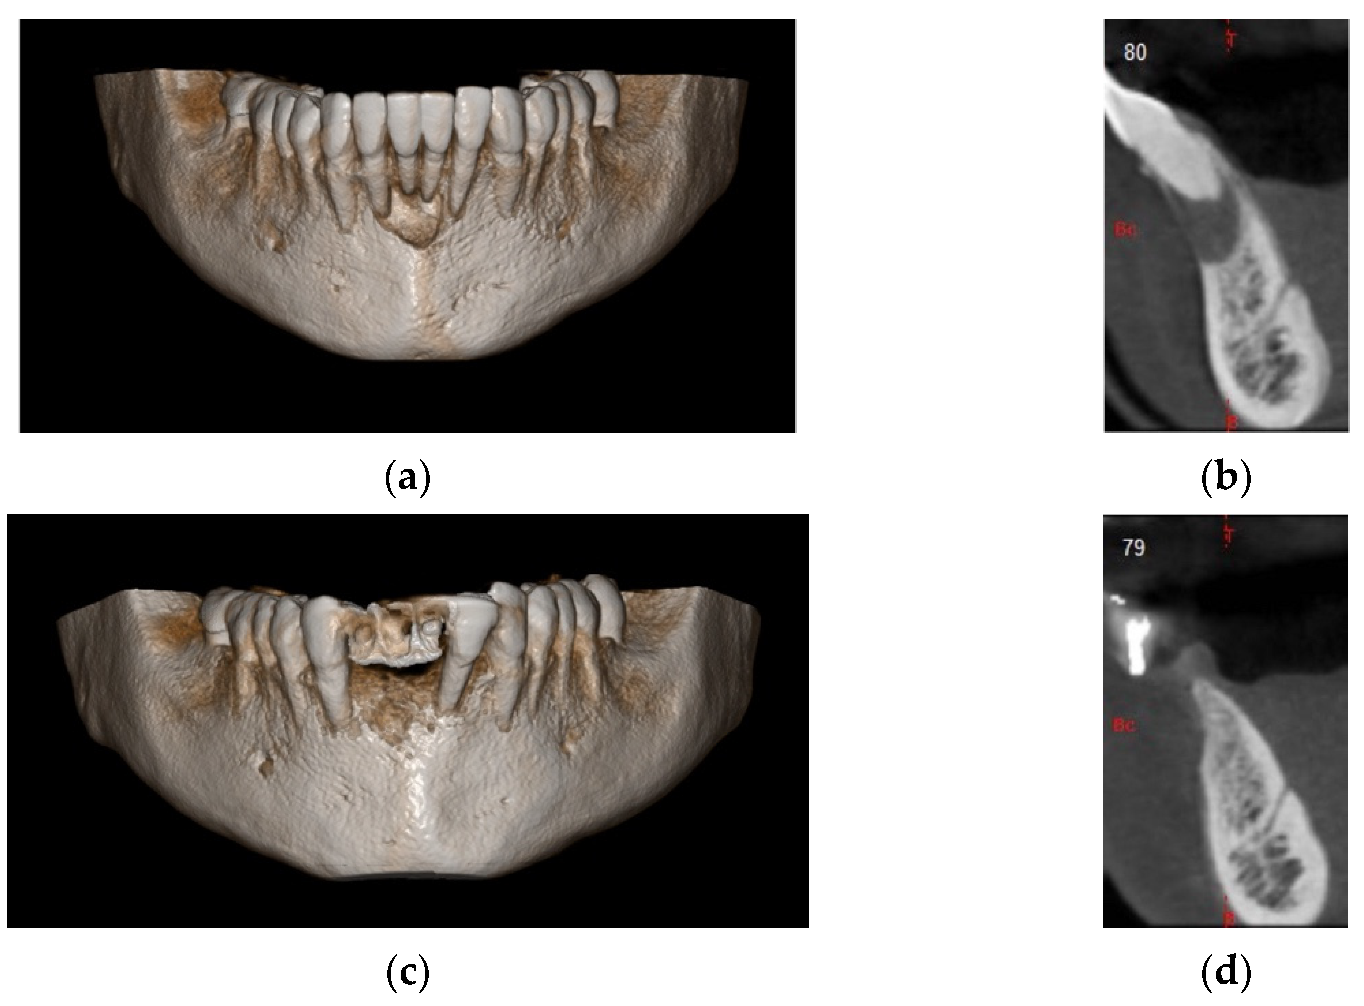

4.1. Clinical Case n.1.

4.2. Clinical Case n.2.

4.3. Clinical Case n.3.

4.4. Clinical Case n.4.

4.5. Clinical Case n.5.